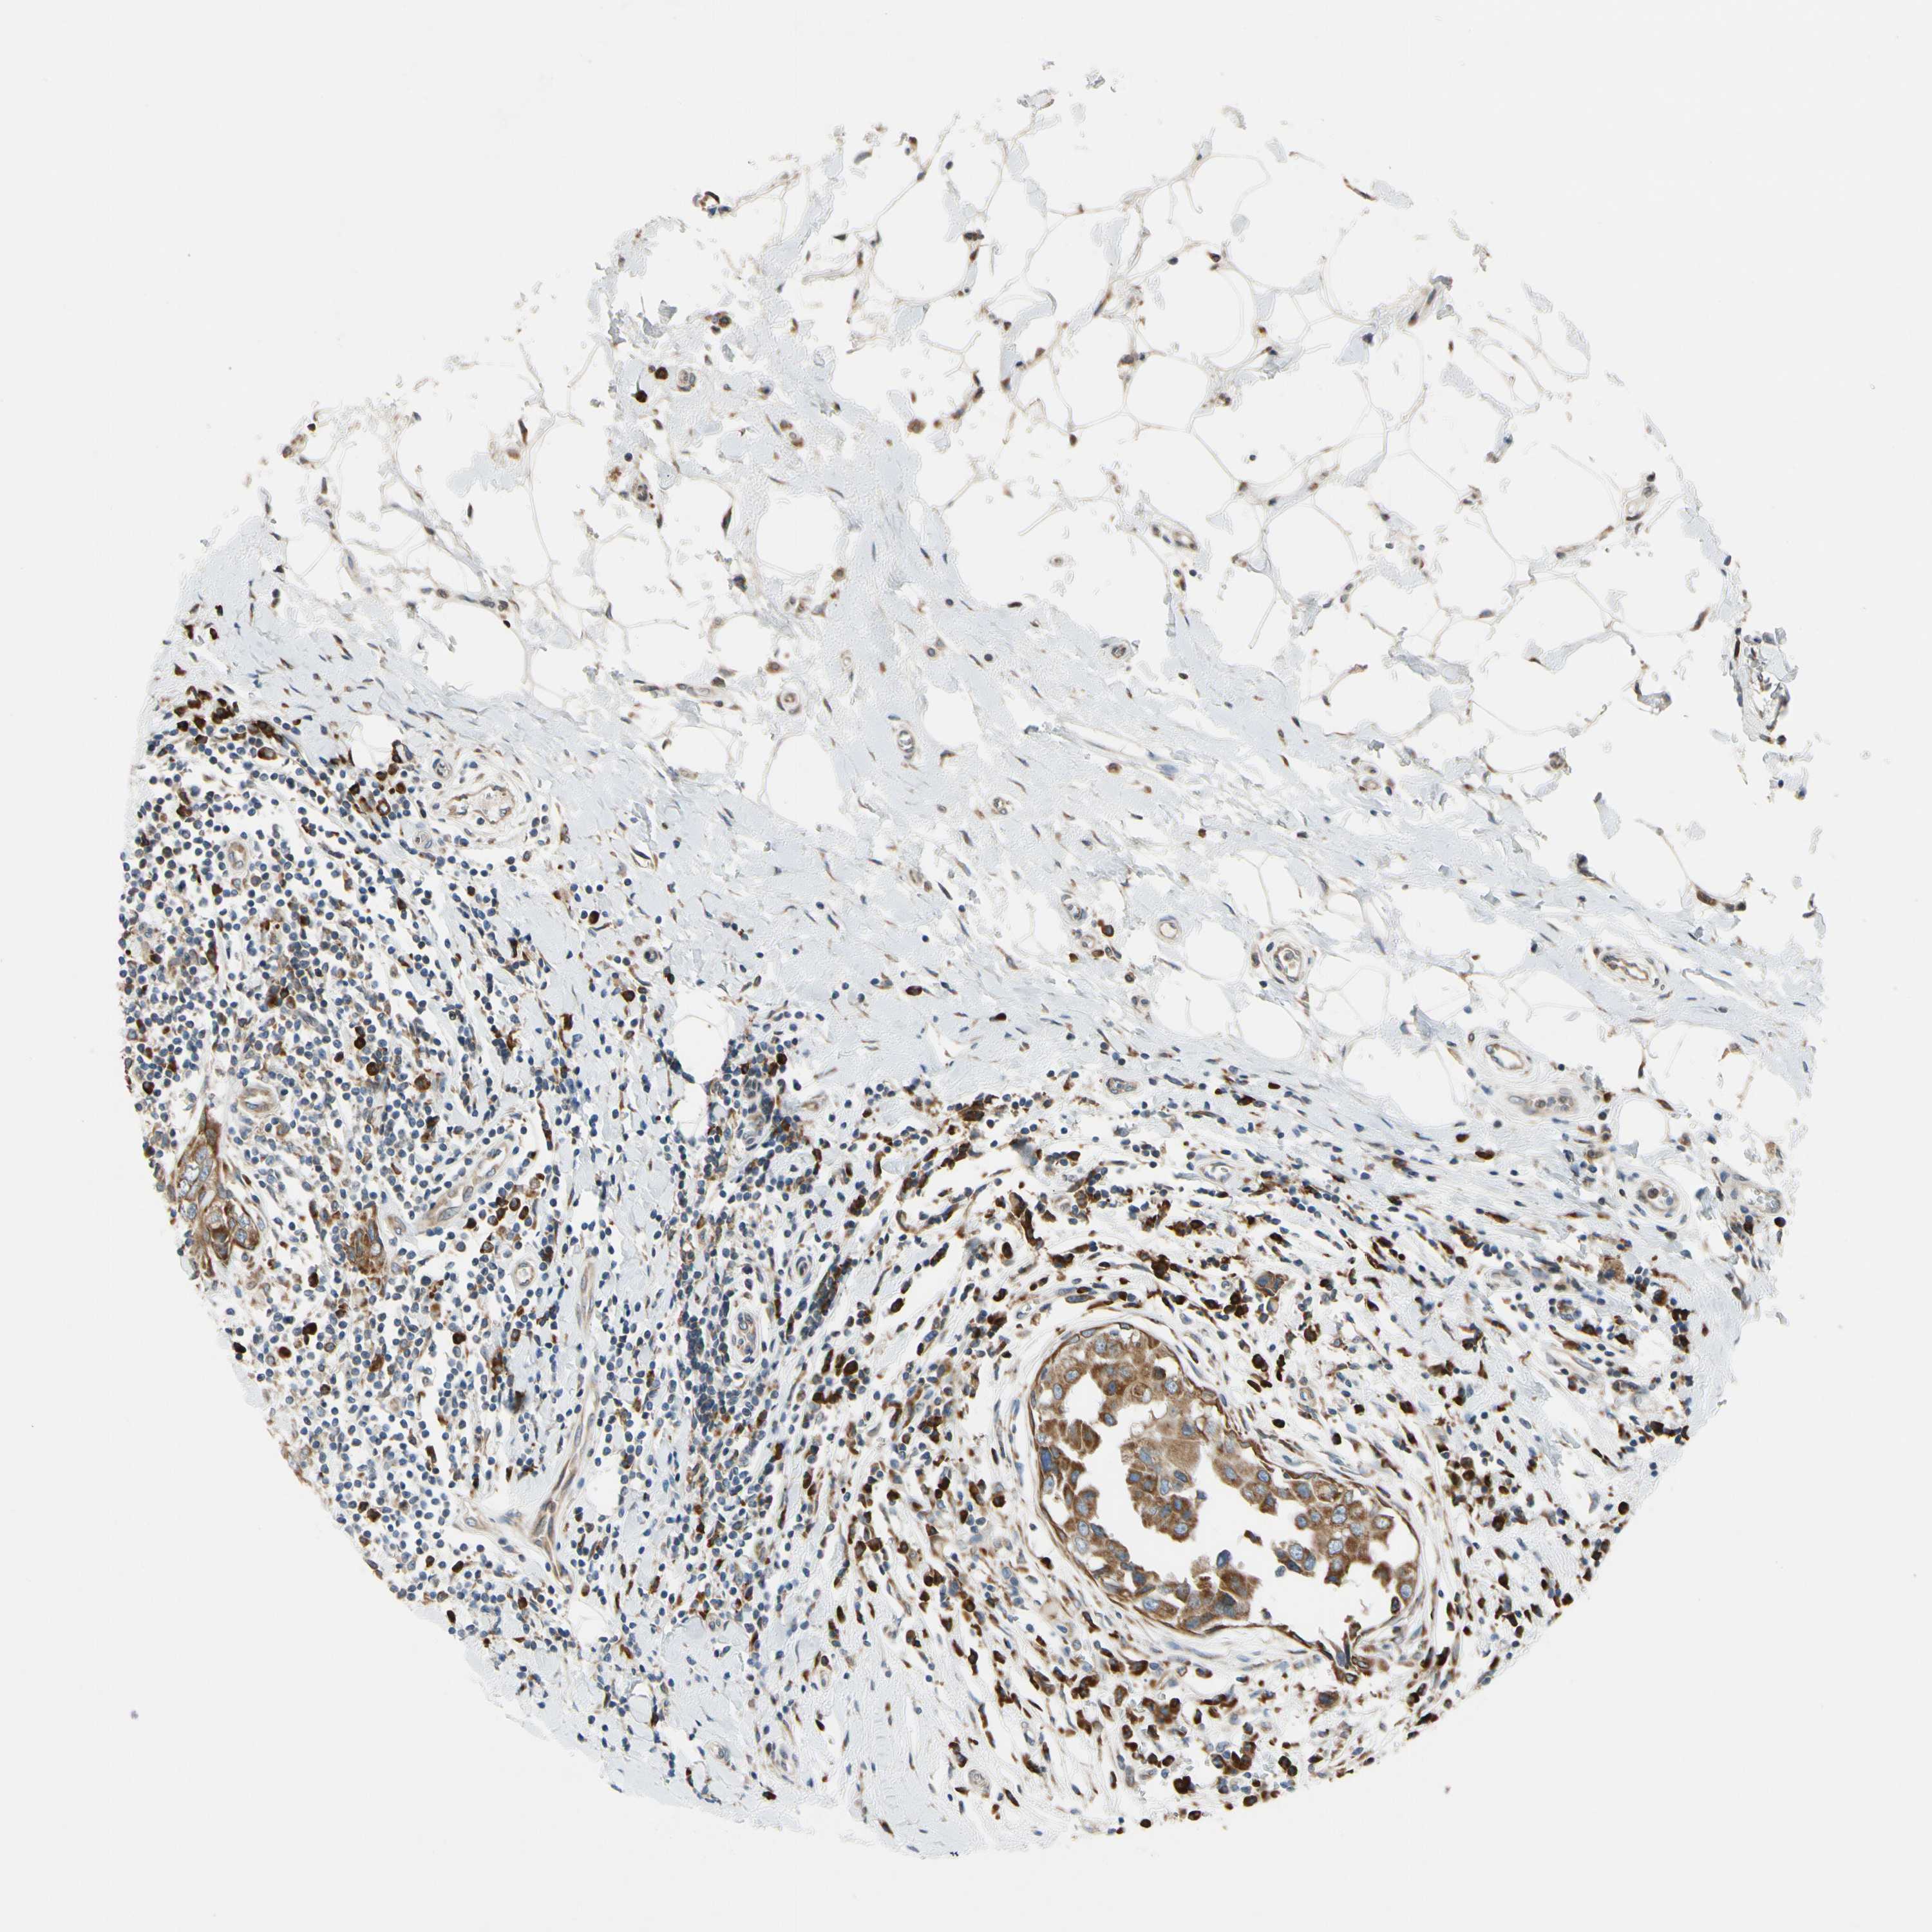

CANCER BREAST CANCER Show tissue menu

BRCA TCGA BRCA VALIDATION PROTEIN EXPRESSION

ANTIBODIES

AND

VALIDATION